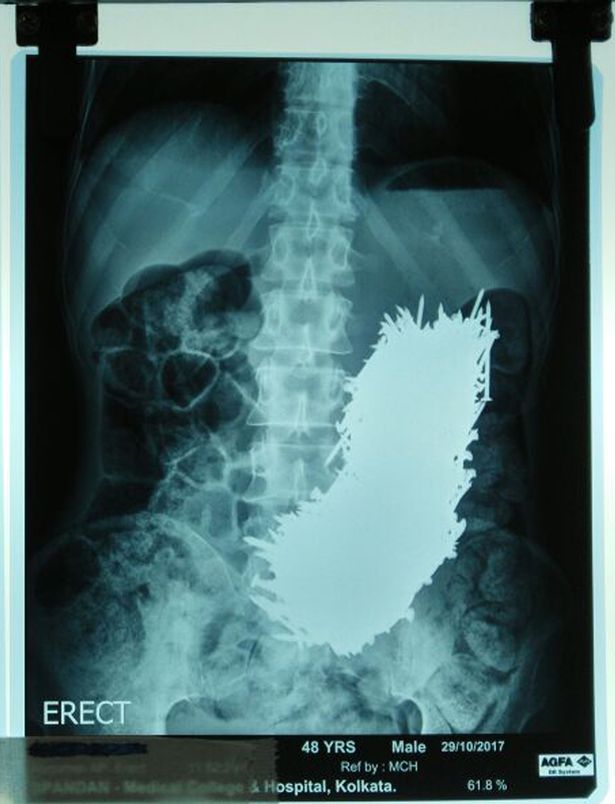

Các bác sĩ đã sốc khi thấy ảnh chụp siêu âm với tổng cộng 600 đinh sắt trong bụng. Sau 2 ngày quan sát, họ quyết định dùng nam châm trong quá trình phẫu thuật, hút đinh sắt ra khỏi bụng bệnh nhân.

Ảnh chụp cho thấy số đinh khổng lồ trong bụng của Pradip